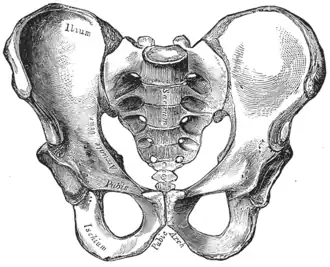

Skeletal structure frames the overall shape of the body and does not alter much after maturity. Males are, on average, taller, but body shape may be analyzed after normalizing with respect to height. The length of each bone is constant, but the joint angle will change as the bone moves.[7] The dynamics of biomechanical movement will be different depending on the pelvic morphology for the same principle. The fascia anatomy of the sides of the sacral diamond area, which regulates its shape and movement, corresponds to the fascial thickenings that are part of the sacral complex of the thoracambular fascia, which surrounds the sacroiliac joints both posteriorly and, from the iliolumbar ligaments, anteriorly. The biochemical properties of the muscular bands have repercussions from the inside to the outside and vice versa.[8] The shape of the posterior muscular and adipose tissues seems to correspond with the general pelvic morphology. The classification is as follows the gynecoid pelvis corresponds to a round buttocks shape, the platypelloid pelvis to a triangle shape, the anthropoid pelvis to a square shape and the android pelvis to a trapezoidal gluteus region.[8] The trapezoidal shape is what gives steatopygia its specific shape and appearance.

Female traits

Widening of the hip bones occurs as part of the female pubertal process,[9] and estrogens (the predominant sex hormones in females) cause a widening of the pelvis as a part of sexual differentiation. Hence females generally have wider hips, permitting childbirth. Because the female pelvis is flatter, more rounded and proportionally larger, the head of the fetus may pass during childbirth.[10] The sacrum in females is shorter and wider, and also directed more toward the rear (see image).[11] This sometimes affects their walking style, resulting in hip sway.[12] The upper limb in females have an outward angulation (carrying angle) at elbow level to accommodate the wider pelvis. After puberty, hips are generally wider than shoulders. However, not all females adhere to this stereotypical pattern of secondary sex characteristics.[13] Males and females generally have the same hormones, but blood concentrations and site sensitivity differs between males and females. Males produce primarily testosterone with small amounts of estrogen and progesterone, while women produce primarily estrogen and progesterone and small amounts of testosterone.[14]